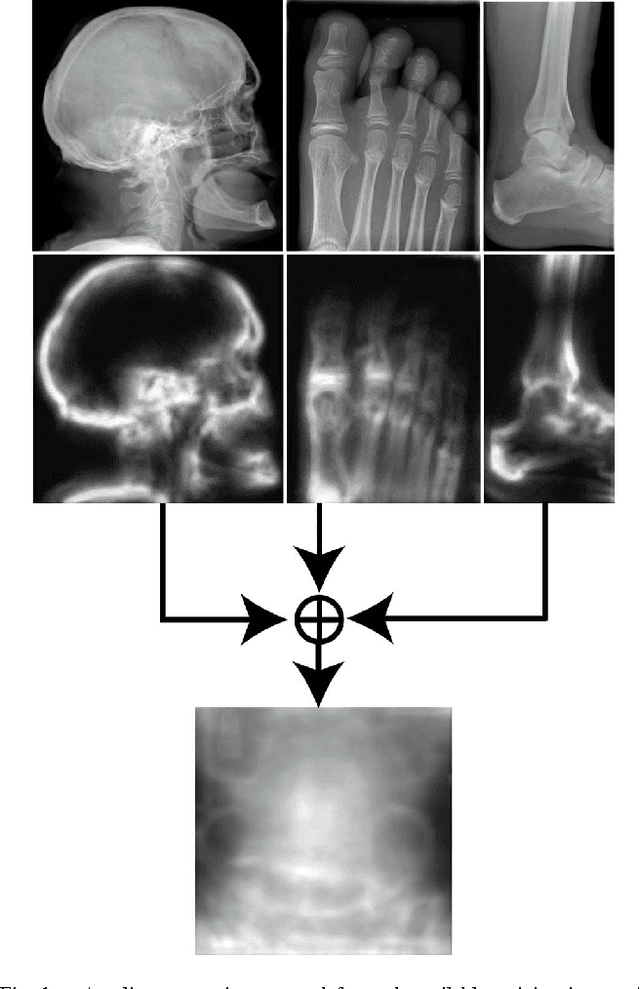

Good results on image classification and retrieval using support vector machines (SVM) with local binary patterns (LBPs) as features have been extensively reported in the literature where an entire image is retrieved or classified. In contrast, in medical imaging, not all parts of the image may be equally significant or relevant to the image retrieval application at hand. For instance, in lung x-ray image, the lung region may contain a tumour, hence being highly significant whereas the surrounding area does not contain significant information from medical diagnosis perspective. In this paper, we propose to detect salient regions of images during training and fold the data to reduce the effect of irrelevant regions. As a result, smaller image areas will be used for LBP features calculation and consequently classification by SVM. We use IRMA 2009 dataset with 14,410 x-ray images to verify the performance of the proposed approach. The results demonstrate the benefits of saliency-based folding approach that delivers comparable classification accuracies with state-of-the-art but exhibits lower computational cost and storage requirements, factors highly important for big data analytics.